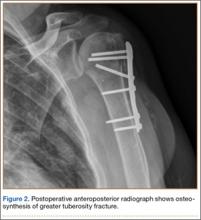

Eleven patients (7 women, 4 men) underwent plate osteosynthesis for an isolated greater tuberosity fracture (Figure 2). Mean age at surgery was 60 years (range, 37-71 years). All patients were right-hand–dominant; 7 of the 11 sustained the injury on the dominant side. For all 11 patients, final postoperative ROM and complications were recorded. No patient required additional surgery. Before injury, all patients felt their shoulder was 100% normal. Nine of the 11 patients were available for assessment of functional outcome and ROM at a mean (SD) of 27 (8) months (range, 16-44 months). At final follow-up, mean (SD) forward elevation was 147° (28°; range, 100°-180°), and mean (SD) external rotation was 25° (15°; range, 10°-60°). Mean (SD) SANE score was 72 (17; range, 50-90), and mean (SD) PSS was 79 (16; range 43-90). On a 1-to-10 scale, patients’ mean (SD) overall satisfaction was 8.6 (1.9; range, 4-10). Of the 9 patients who worked before injury, 8 returned to preoperative duty. Six patients reported stiffness (consistent with ROM). All patients said they would have the surgery again (Table).